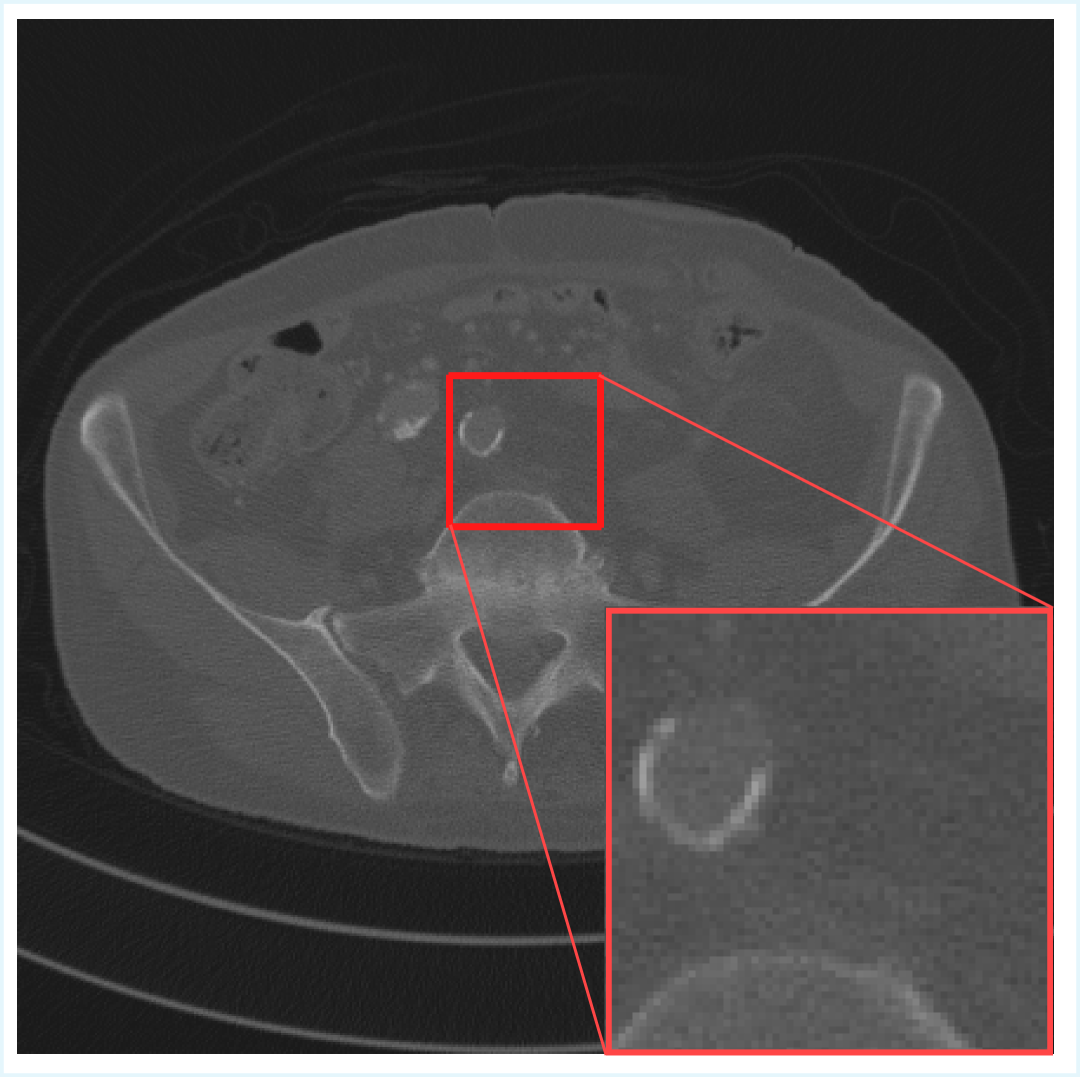

This process yielded a total of 16,628 spatially aligned pairs of LDCT and NDCT slices. This pre-processing ensures consistency and comparability across experiments, allowing reliable assessment of image enhancement performance. An illustrative example of the dataset is shown in Figure 1.

Figure 1: Images (a) and (b) show full 512×512512\times 512 CT slices for LDCT and NDCT, respectively, with a highlighted 96×9696\times 96 region indicated by the red box.